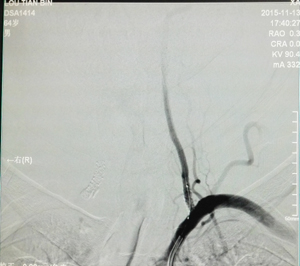

图为左侧椎动脉起始段狭窄手术前DSA 图为右侧椎动脉起始段狭窄手术前DSA